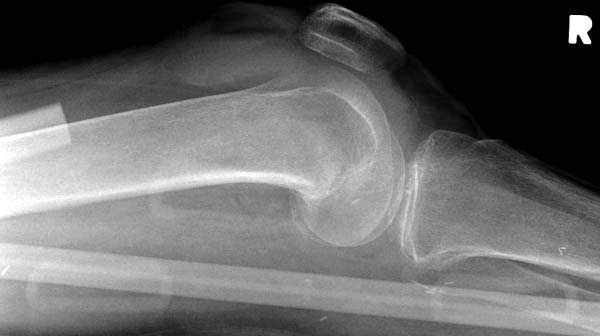

Такие “чужие осложнения” встречаются у всех и представляю банальный случай, который шаг за шагом показано как перерос в более сложный процесс... Больная 70 лет, множественные ко-морбидности, чрезвертельный перелом первоначально фиксирован Гамма 3. Осложнение в течение 6 недель, ревизия тотальной артропластикой и во время установки ножки обнаружена трещина диафиза (17), из малого доступа фиксация алло-графтом.

Обычно после чрезвертельных переломов, за исключением молодых, у пожилых остается нестабильность при движении. Часто падают и после 3х мес. в результате падения обнаружен перипротезный перелом (22-23), который зафиксирован Синтез пластиной.

Повторно поступает после двух с половиной лет, где обнаруживается перелом на второй стороне. Немного сложно, но для фиксации выбрали Antegrade InterTan Smith Nephew Nail и с момента фиксации более 3х мес.